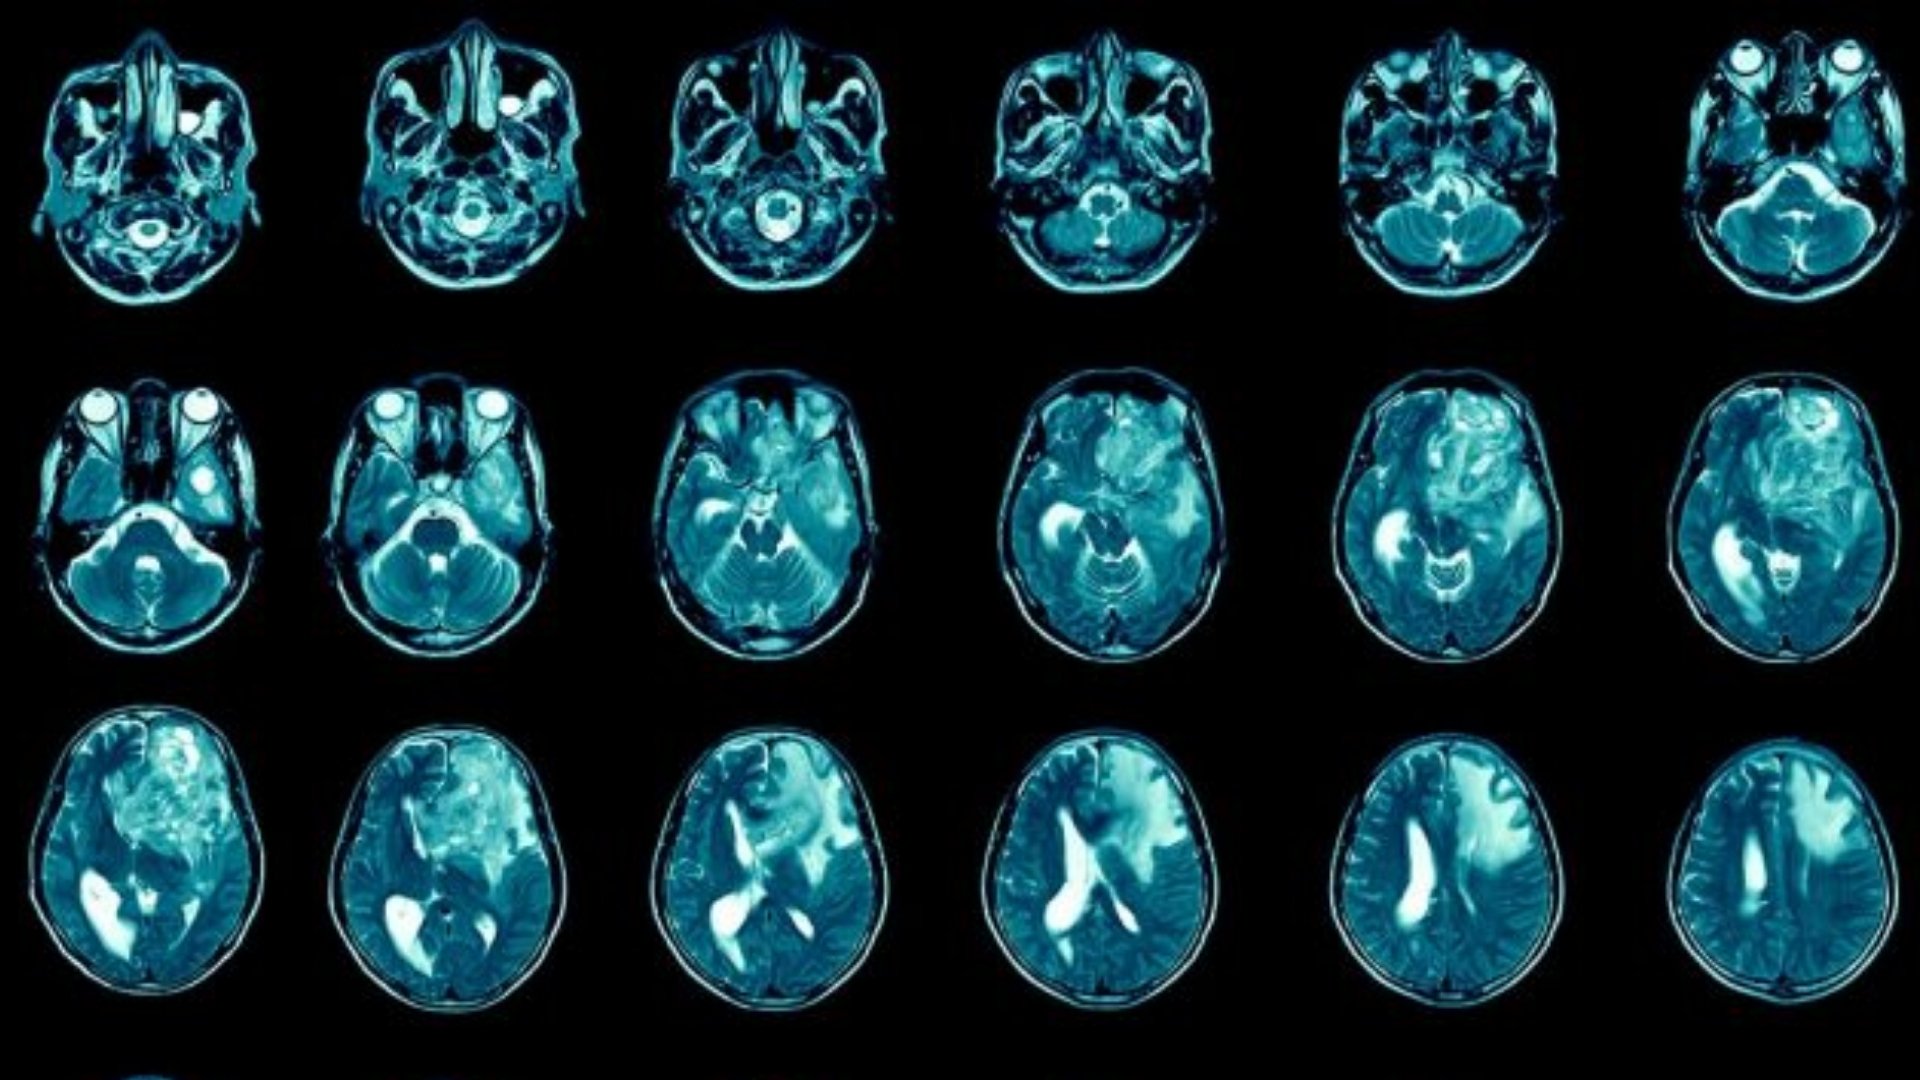

什麼是膠質母細胞瘤 (GBM)?

膠質母細胞瘤 (GBM) 是最具侵襲性的原發性腦癌,起源於膠質細胞 - 神經元周圍的支持性組織。Glioblastoma (GBM) 腫瘤的特徵是細胞快速增殖和顯著的新陳代謝變化,嚴重依賴葡萄糖新陳代謝。具體來說,GBM 腫瘤細胞呈現沃伯格效應 (Warburg effect),癌細胞的葡萄糖代謝率比正常細胞高出 200 倍,從根本上改變了細胞的能量平衡和增殖。

及早發現症狀可顯著改善膠質母細胞瘤 (GBM) 的預後和治療效果。膠質母細胞瘤 (GBM) 通常會出現腦內位置相關的症狀,通常是由於顱內壓增高和局部組織破壞所致。

膠質母細胞瘤 (GBM) 的症狀與腫瘤的生物學特性和位置直接相關。舉例來說,靠近腦部語言中心的腫瘤通常會造成語言障礙,而靠近運動皮層區域的腫瘤則會造成肌肉無力和行動不便。